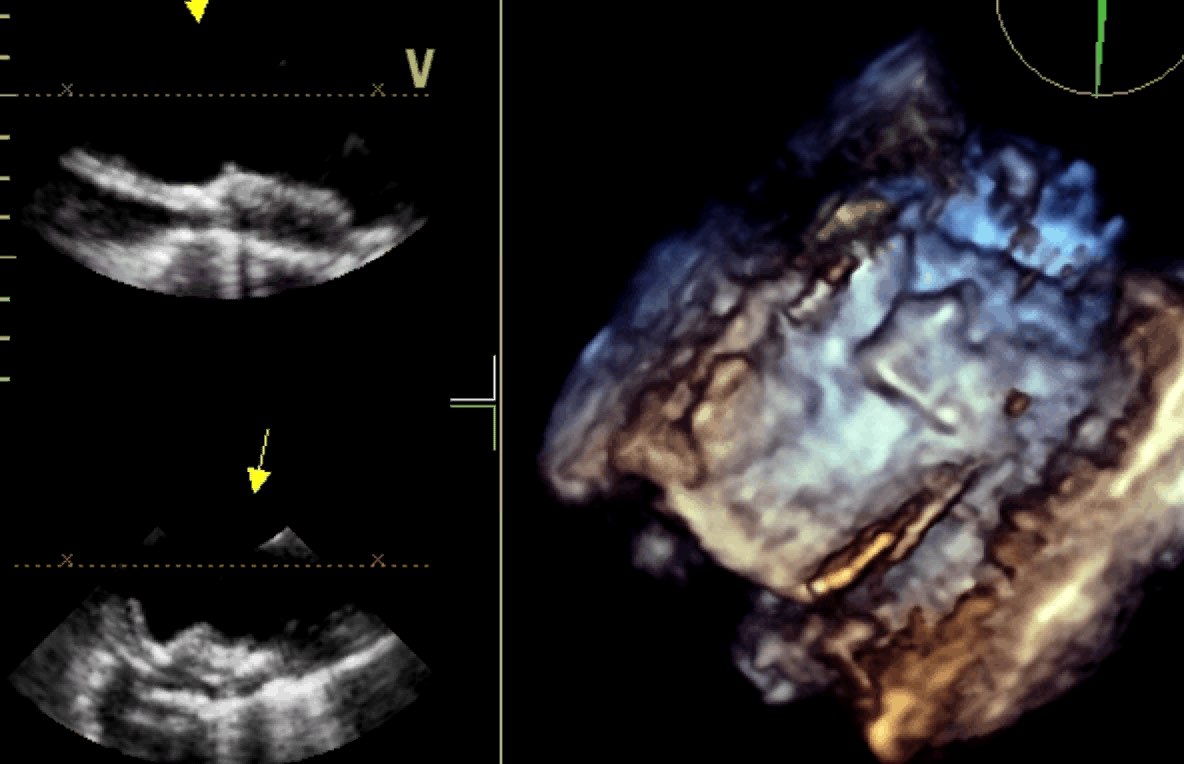

Aorta con placca ulcerata